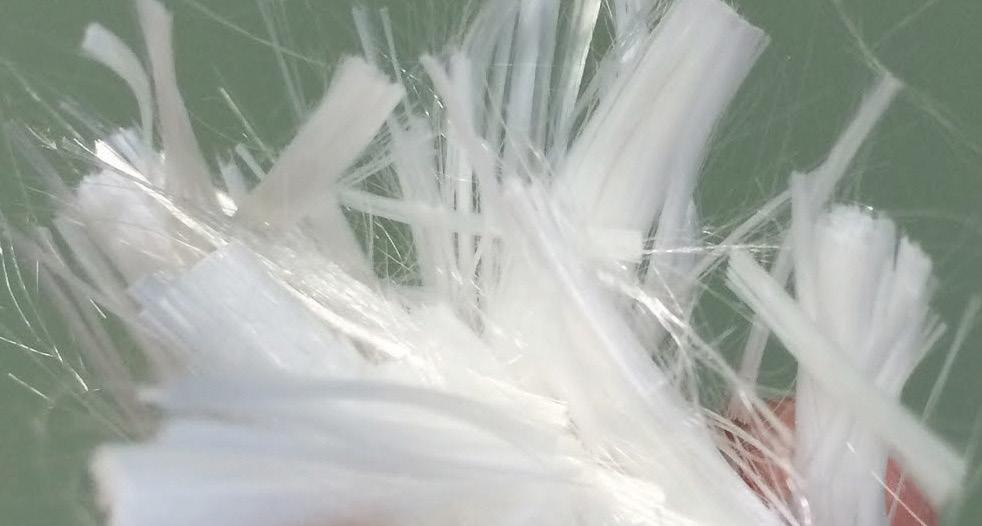

VISUALIZING SLIMER AT WORK

DISTRIBUTION OF SLIMER THROUGHOUT SQUAMOUS AND GLANDULAR REGIONS

DISTRIBUTION OF SLIMER (without color dye) SHOWING PRODUCT GRANULARITY

The above gastroscopy images show Slimer coating the stomach. The horses received 2oz of Slimer via syringe and then lunged at the walk and trot for 10-15 minutes to simulate splashing acid while being ridden. Though Slimer is brown, it was initially dyed blue to be more visible. In order to show that the blue dye did not discolor the stomach or disassociate from Slimer, over 90cc of water was inserted through the gastroscope to “rinse” a portion showing that the underlying tissue remained pink.

DEMARCATION AREA RINSED WITH WATER HIGHLIGHTING SLIMER’S GRANULARITY

DISTRIBUTION OF SLIMER (without color dye) THROUGHOUT SQUAMOUS AND GLANDULAR REGIONS